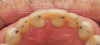

A 75-year-old man presented to the office with severe anterior tooth wear (Figure 2). After meticulous record-taking and thorough planning, a treatment plan was established to rehabilitate the patient to prevent further breakdown. The treatment plan consisted of crowns for teeth Nos. 4 through 13, 20, 21, 28, and 29 coupled with anterior incisal composites for teeth Nos. 22 through 27. Composites were utilized for cost savings to the patient and as a way to establish a more stable occlusion. It was explained to the patient that the composites could be transitioned to veneers at a later date if and when he desired to do so.